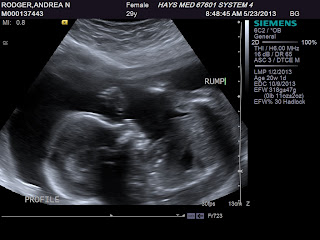

Last Monday, I had another sono to check my fluid levels and so we got to see Miss thing again! Which I loved. Sean was swamped at work, so he didn't get to see her but we got a few cute profile pics. My favorite is the 2nd to last of her nose and mouth! She was also yawning during the sono which was cute too. Unfortunately right now the little stinker is breech. So she best be finding a way to turn around before her due date! She weighed in around 2.2 lbs and was measuring around 26 weeks 1 day. (I'm technically 26 and 5 days.). She is also still very much a girl! :) Oh, and her heartbeat was 135. I compared her to Lyla who had I had to have a sono with at 28 weeks and Lyla was 2.8 lbs and her hb was 136. So they are pretty similar! Oh, and my fluid levels were higher, so everything is good there too!

And without further ado, Miss Baby Jay 3.0 at 26 weeks!

My favorite. Up by her head is her hand as she kept her hands next to her face most of the time. Lyla did the same thing!